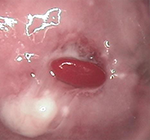

治疗前